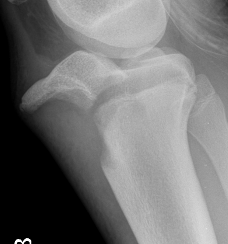

Ogden Classification

A: Undisplaced

B: Displaced

| Type I | Type II | Type III | Type IV |

|---|---|---|---|

| Avulsion distal tibial tubercle | Extension into tibial physis but not into knee joint | Extension across tibial physis and into knee joint | Extends posteriorly across tibial physis |

| Disrupts extensor mechanism | Disrupts extensor mechanism |

Disrupts extensor mechanism Disrupts articular surface Disrupts growth plate |

|

Associated Osgood-Schlatter Second most common |

Most common Risk of compartment syndrome |

Risk of compartment syndrome |

Type IB

Type IIB

Type III

Comminuted Type III